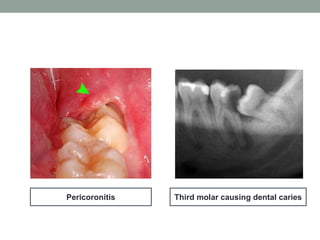

• Infections: Removal of any symptomatic impacted tooth

should be considered with food impaction causing

halitosis, especially where there have been one or more

episodes of infection such as pericoronitis(75-80% of

patients with impacted third molar develop pericoronitis),

cellulitis, abscess formation; or untreatable

pulpal/periapical pathology.

• Unrestorable caries: Removal should be considered

when there is caries in the impacted tooth or when there

is caries in the adjacent second molar tooth which cannot

be satisfactorily treated without removal of the third molar.

Third molar causing dental cariesPericoronitis